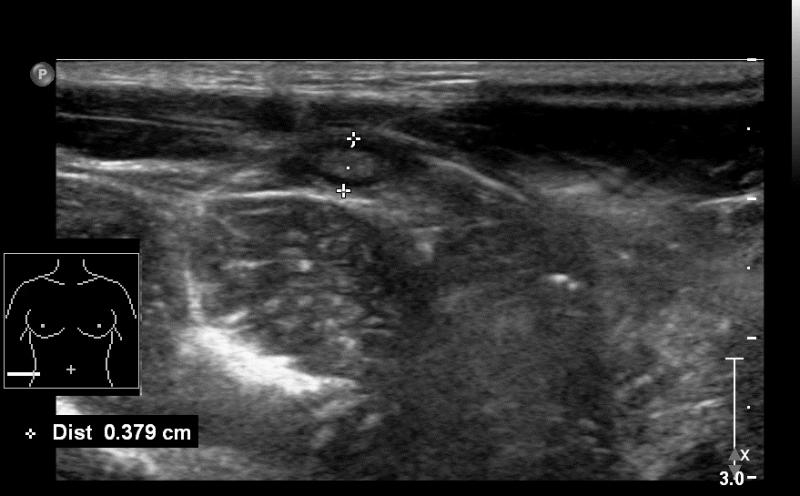

Przypadek 48: 8-letni pacjent z bólami brzucha Rozpoznanie: W badaniu usg uwidoczniono prawidłowy wyrostek robaczkowy (zaznaczony markerami).